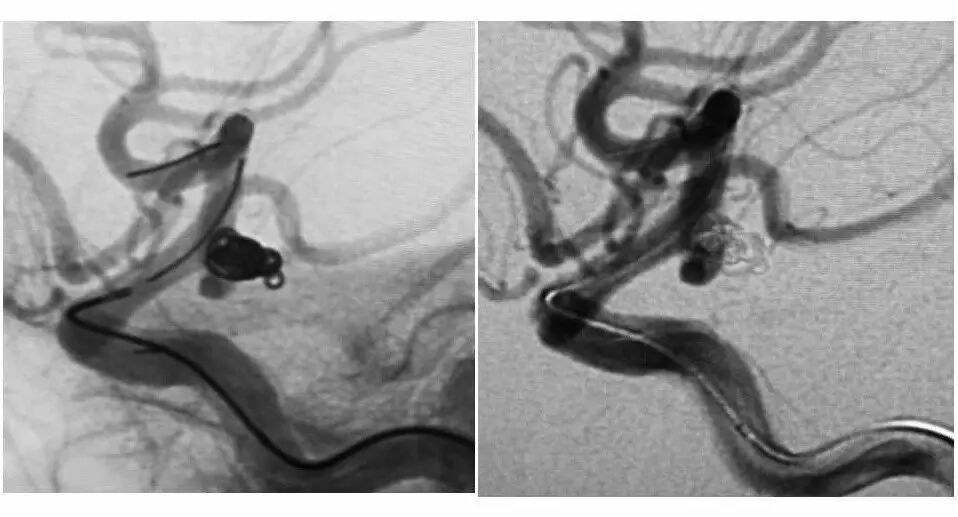

今天为大家分享的是“强生医疗CNV-神经介入专栏”第十五期,由首都医科大学宣武医院何川教授带来的“颅内动脉瘤介入治疗”精彩讲课视频及PPT,欢迎观看、阅读。文章仅代表作者个人观点,如有不同见解,欢迎同道斧正!

何川 ,首都医科大学宣武医院副主任医师,中国医师协会神经介入专业委员会常务委员,长期从事脑血管病和脊髓血管病的手术及介入治疗和相关研究工作。首都医科大学神经外科博士,师从于中国神经介入开创人凌锋教授;日本东北大学医院脑血管病治疗科博士后,师从于日本国脑血管病血管内治疗的开创者高桥教授。